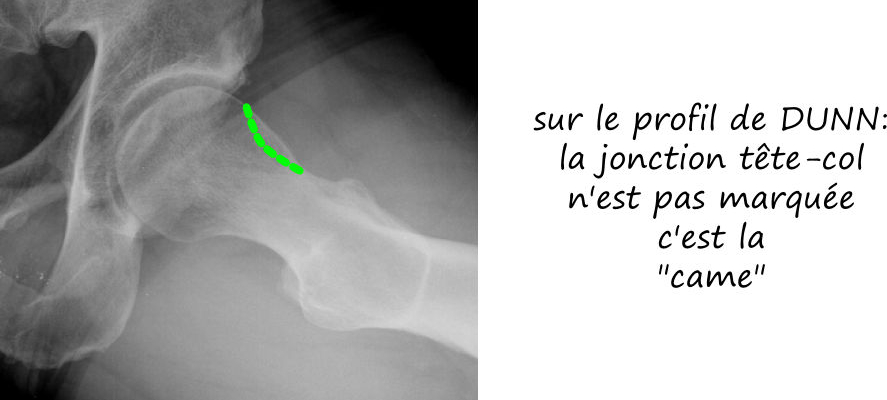

- par effet came: le facteur prédominant est l’excroissance osseuse de la face antérieure du col fémoral

Le conflit fémoro acétabulaire se décèle sur de simples radiographies de la hanche, notemment sur le profil de DUNN qui expose la face antérieure du col fémoral. Sur cette radio est estimée l’angle alpha, correpondant à l’angle formé par l’axe du col fémoral et une droite passsant par le centre de la tete fémorale et le point de décrochage de la jonction tete-col, et qui est normalement de l’ordre de 45°; il est augmenté dans les conflits par effet came, comme sur cette radio ci dessous.